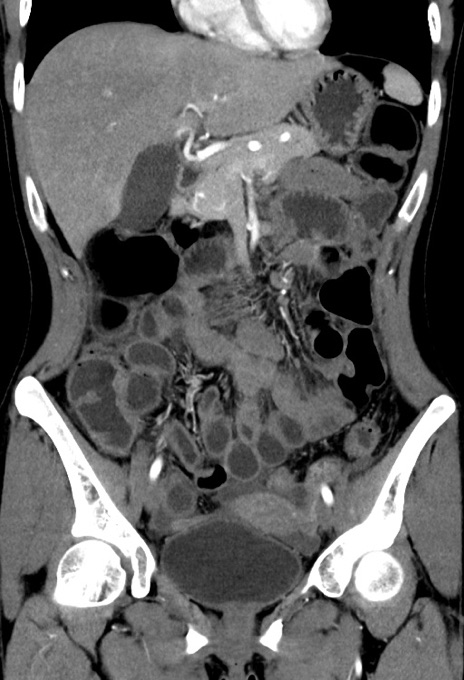

症例17(冠状断像)

【症例】20歳代女性

【主訴】嘔吐、下腹部痛

【現病歴】昨日夕食後に嘔吐し下腹部痛が出現。本日になっても嘔吐持続し改善しないため来院。

【身体所見】意識清明、BT 37.2℃、BP 108/67mmHg、腹部:平坦、やや硬、下腹部正中から右にかけて圧痛あり、反跳痛軽度あり、tapping pain(+)。

【データ】WBC 13600、CRP 14.94